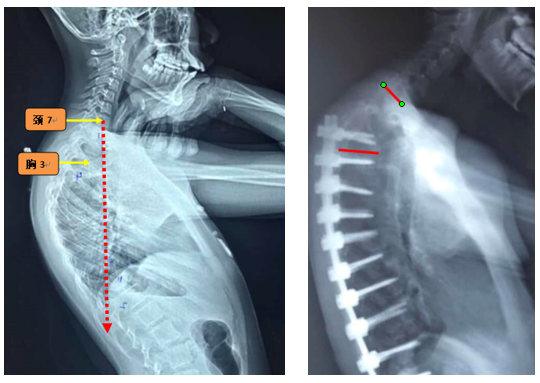

图6 长节段融合固定上固定椎(UIV)选择在胸10-12胸腰椎交界区是PJK的风险因素之一

Ø 颈7铅垂线距离UIV太远

图19 颈7铅垂线距离UIV太远